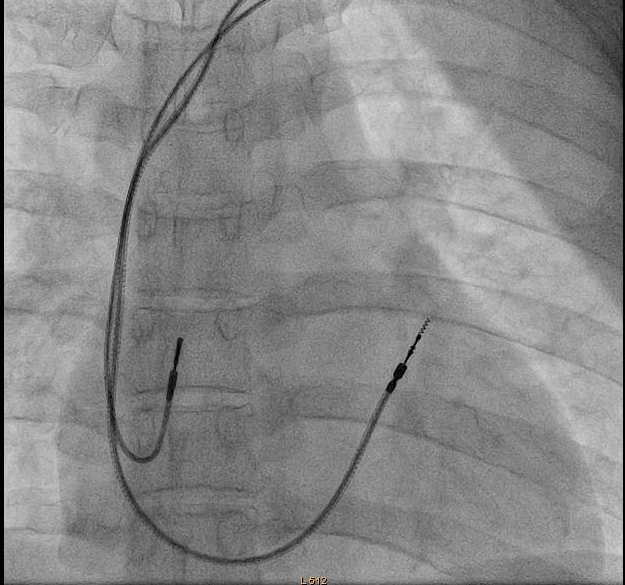

Puncture with venogram